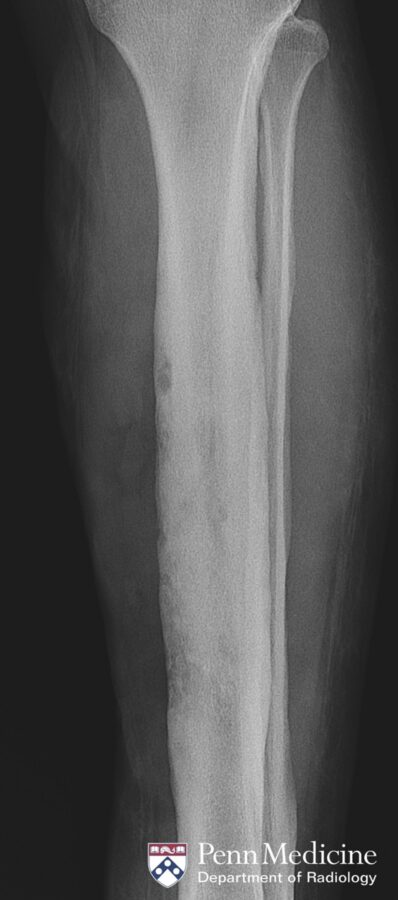

35-year-old woman with progressive pain and swelling in left lower leg

A 35-year-old woman presented to the emergency department with a three-week history of progressive pain and swelling in her left lower leg.

Published Date: February 13, 2026

Tags:

Body

,

CT

MRI

Musculoskeletal

X-Ray